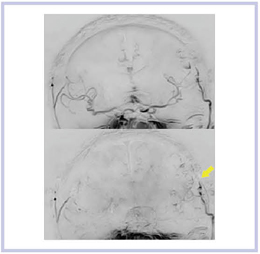

3)MR DSA

図10は,Titan 3Tによる髄膜腫のMR DSAである。撮像マトリックスの精度を1.5Tよりも上げたため,時間分解能は約1秒になったが,腫瘍は良好に増強されている。正常動脈の末梢,あるいは脳表静脈の細部までよく描出されている。

図10 髄膜腫のMR DSA